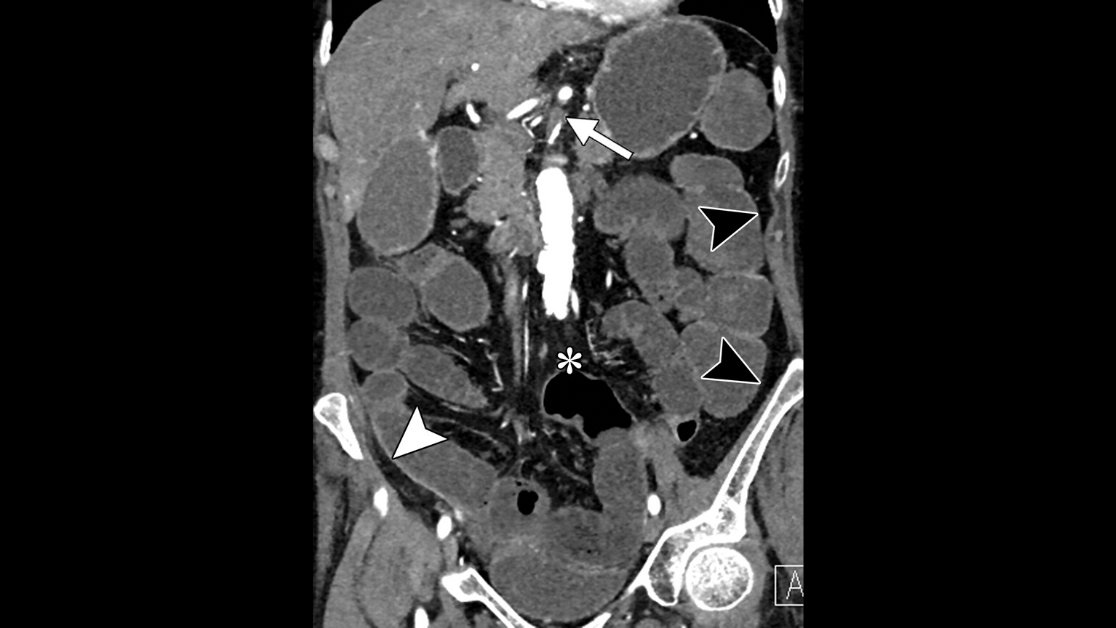

Ischemic bowel from internal hernia on #SpectralCT. Diagnosis made, surgeon called, <60 min from pt entering ER.

Confirmed on surgery, bowel ischemic but viable. Speed saves!

Also, imagine delaying this because you insist on giving PO contrast...